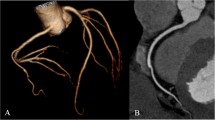

A total of 3,060 coronary artery segments with a vessel diameter of at least 1.5 mm were accessible for evaluation. An overall diagnostic image quality was found in 94.99% of all segments (2,907), while 5.01% of all segments (153) were non-evaluative (Table 3). The interobserver agreement for subjective image quality was excellent (kappa = 0.93). There were significant differences in the rate of non-diagnostic segments between DECT vs. 16- slice CT (p < 0.01; 18 vs. 123 segments) and DSCT vs. 16- slice CT (p < 0.01; 10 vs. 123 segment, Fig. 1). We observed no significant difference for diagnostic image quality between DECT vs. DSCT (p = 0.10; 18 vs.10 segments).

Image examples of the right coronary artery (RCA) in a curved-planar reconstruction in representative coronary CT angiography studies of group 1–3. (a) 58-year-old man from group 1 with an average heart rate of 60 bpm examined with retrospectively ECG gated 16-slice CT (estimated radiation dose 11,8mSV). Image quality was considered diagnostic in all segments of the RCA. (b) 64-year-old woman from group 2 with an average heart rate of 65 bpm examined with retrospectively ECG gated dual source CT. Image quality was diagnostic in all segments and radiation dose estimate was 9,6 mSv. (c) 58-year-old woman from group 3 with an average heart rate of 62 bpm examined with retrospectively ECG-triggered dual source CT in dual energy mode. Estimated radiation dose was 4.6 mSv and image quality was diagnostic in all segments

The image noise (i. e. the standard deviation of the attenuation of air anterior to the sternum) was significantly lower for Group 2 DSCT (mean: 20.2 HU +/− 18.4) compared with group 1 (16-slice CT mean: 23.9 HU +/− 17) and group 3 (DECT mean: 29 HU +/− 21); differences between the 16-slice CT and the DECT were insignificant (p = 0.93) (Table 4, Fig. 1). The CNR in the RCA was significantly (p < 0.01) different in all groups (Table 4). There was no significant difference in CNR of the LCA between group 2 and group 3. The SNR was significantly higher in group 2 compared to group 1 and group 3. However, differences between group 1 and group 3 were insignificant (Table 4).